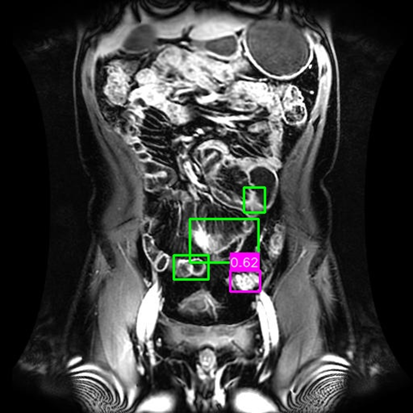

(a) Mask R-CNN [He2017MaskRCNN]

(b) DiffusionDet [Chen2023DiffusionDet_ICCV]

(c) DeFloMat (Ours)

Figure 3: Qualitative Comparison on Crohn’s Disease MRE Test Set. The figure compares detection results from (a) Mask R-CNN, (b) DiffusionDet (S=3S=3), and (c) DeFloMat (Ours, S=3S=3) on challenging MRE slices. Green boxes indicate True Positives (TP, IoU 0.1\geq 0.1), Red boxes indicate False Positives (FP), and Purple boxes indicate False Negatives (FN). DeFloMat consistently demonstrates superior localization quality and sensitivity: it successfully detects subtle inflammation regions (TP) that are often missed (FN, Purple boxes) by the Mask R-CNN baseline (Row 2, 4). Furthermore, DeFloMat provides tighter bounding box localization compared to DiffusionDet, confirming the benefit of learning the direct, deterministic flow field. The results show DeFloMat’s robustness in capturing varying sizes and numbers of inflammatory lesions.

Qualitative Assessment.

Figure 3 provides visual evidence of the models’ performance on challenging MRE slices, where inflammatory lesions can be subtle or obscured. The qualitative results underscore DeFloMat’s enhanced localization fidelity. In challenging cases (e.g., Row 2 and 4), Mask R-CNN and DiffusionDet frequently produce False Negatives (FN, Purple boxes), failing to detect clear inflammation sites. In contrast, DeFloMat reliably converts these FNs into True Positives (TP, Green boxes) by providing tighter and more accurate bounding box predictions. This suggests that the deterministic velocity field learned via Flow Matching is highly effective at precisely directing the proposal centers towards the true lesion locations, a characteristic that is vital for accurate clinical reporting. DeFloMat’s ability to achieve such precise localization with only S=3S=3 steps highlights its clinical utility for rapid diagnostic auxiliary systems.